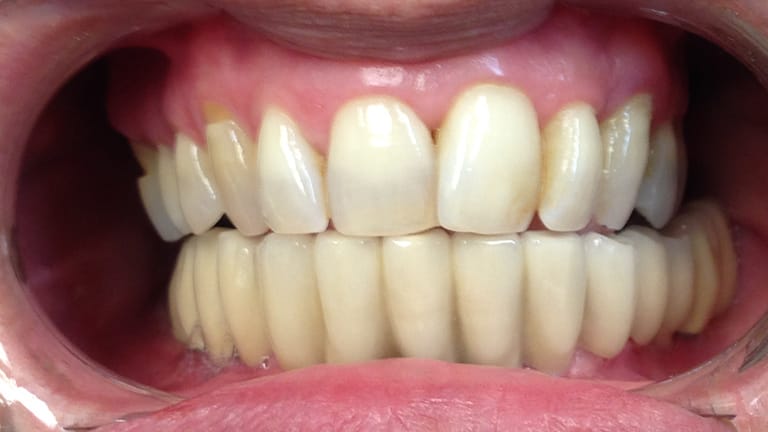

Below is a few examples of what DENTAL IMPLANTS can do for you and your smile!